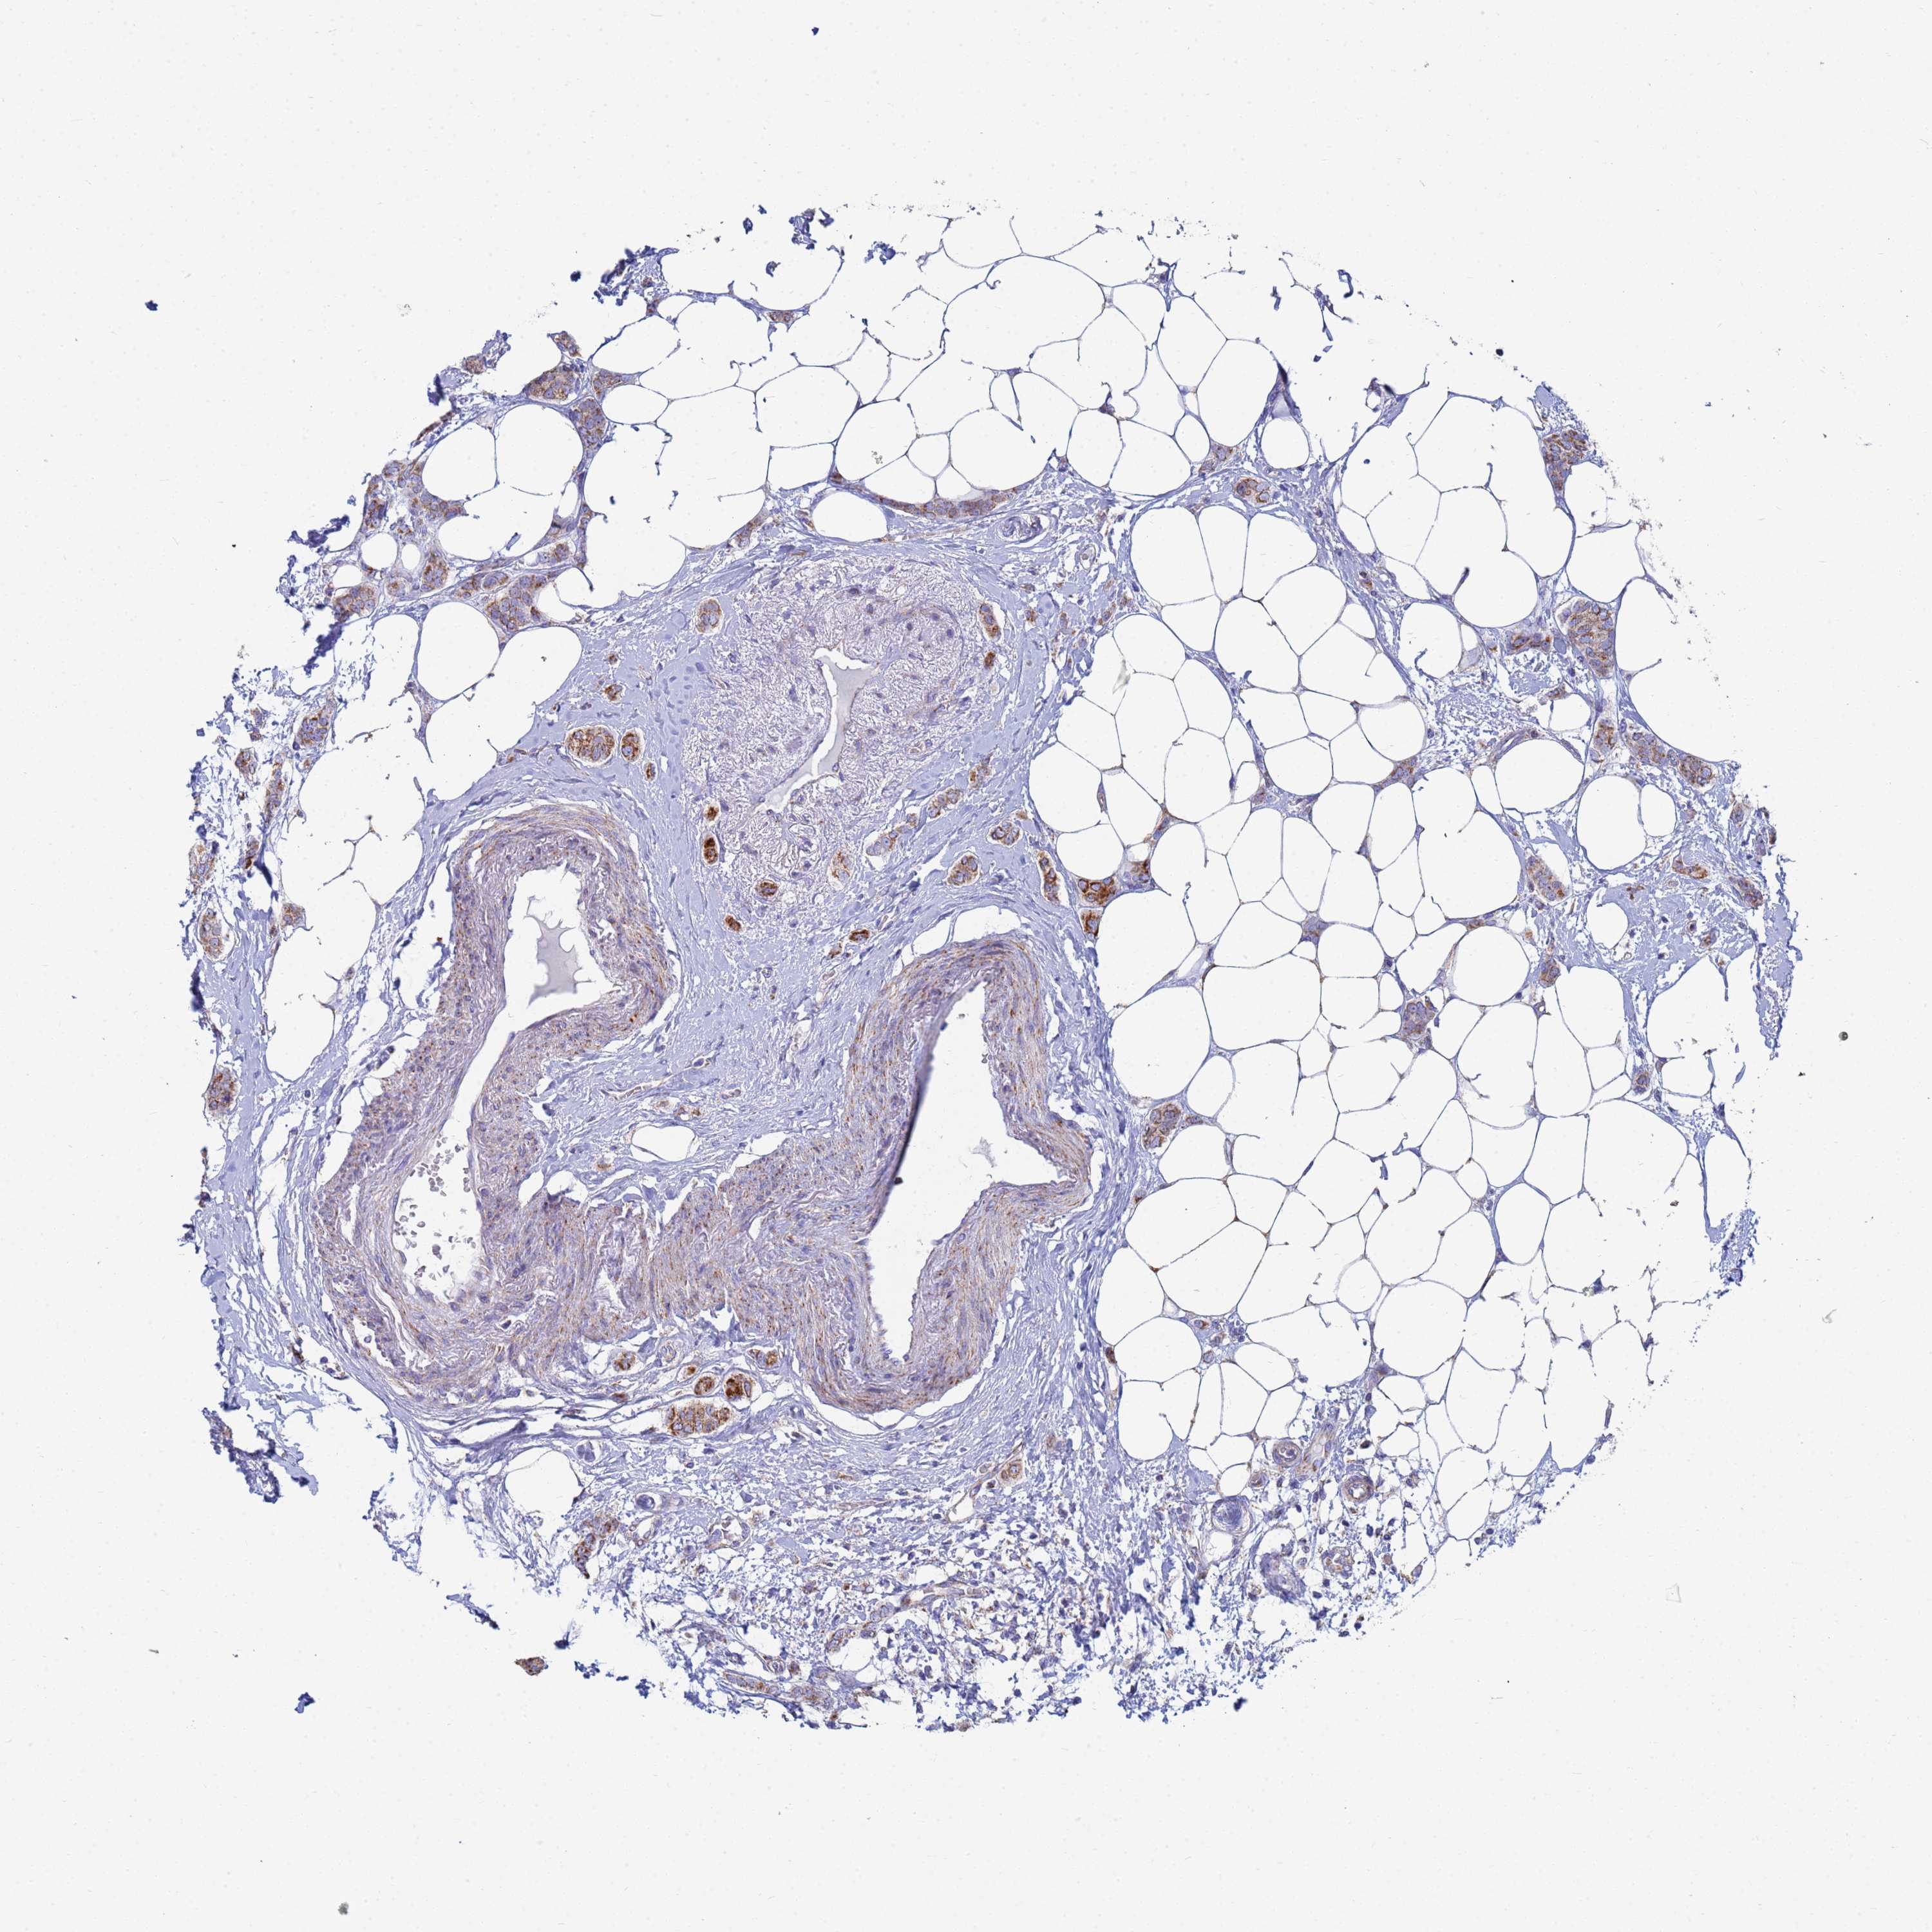

CANCER BREAST CANCER Show tissue menu

BRCA TCGA BRCA VALIDATION PROTEIN EXPRESSION

ANTIBODIES

AND

VALIDATION